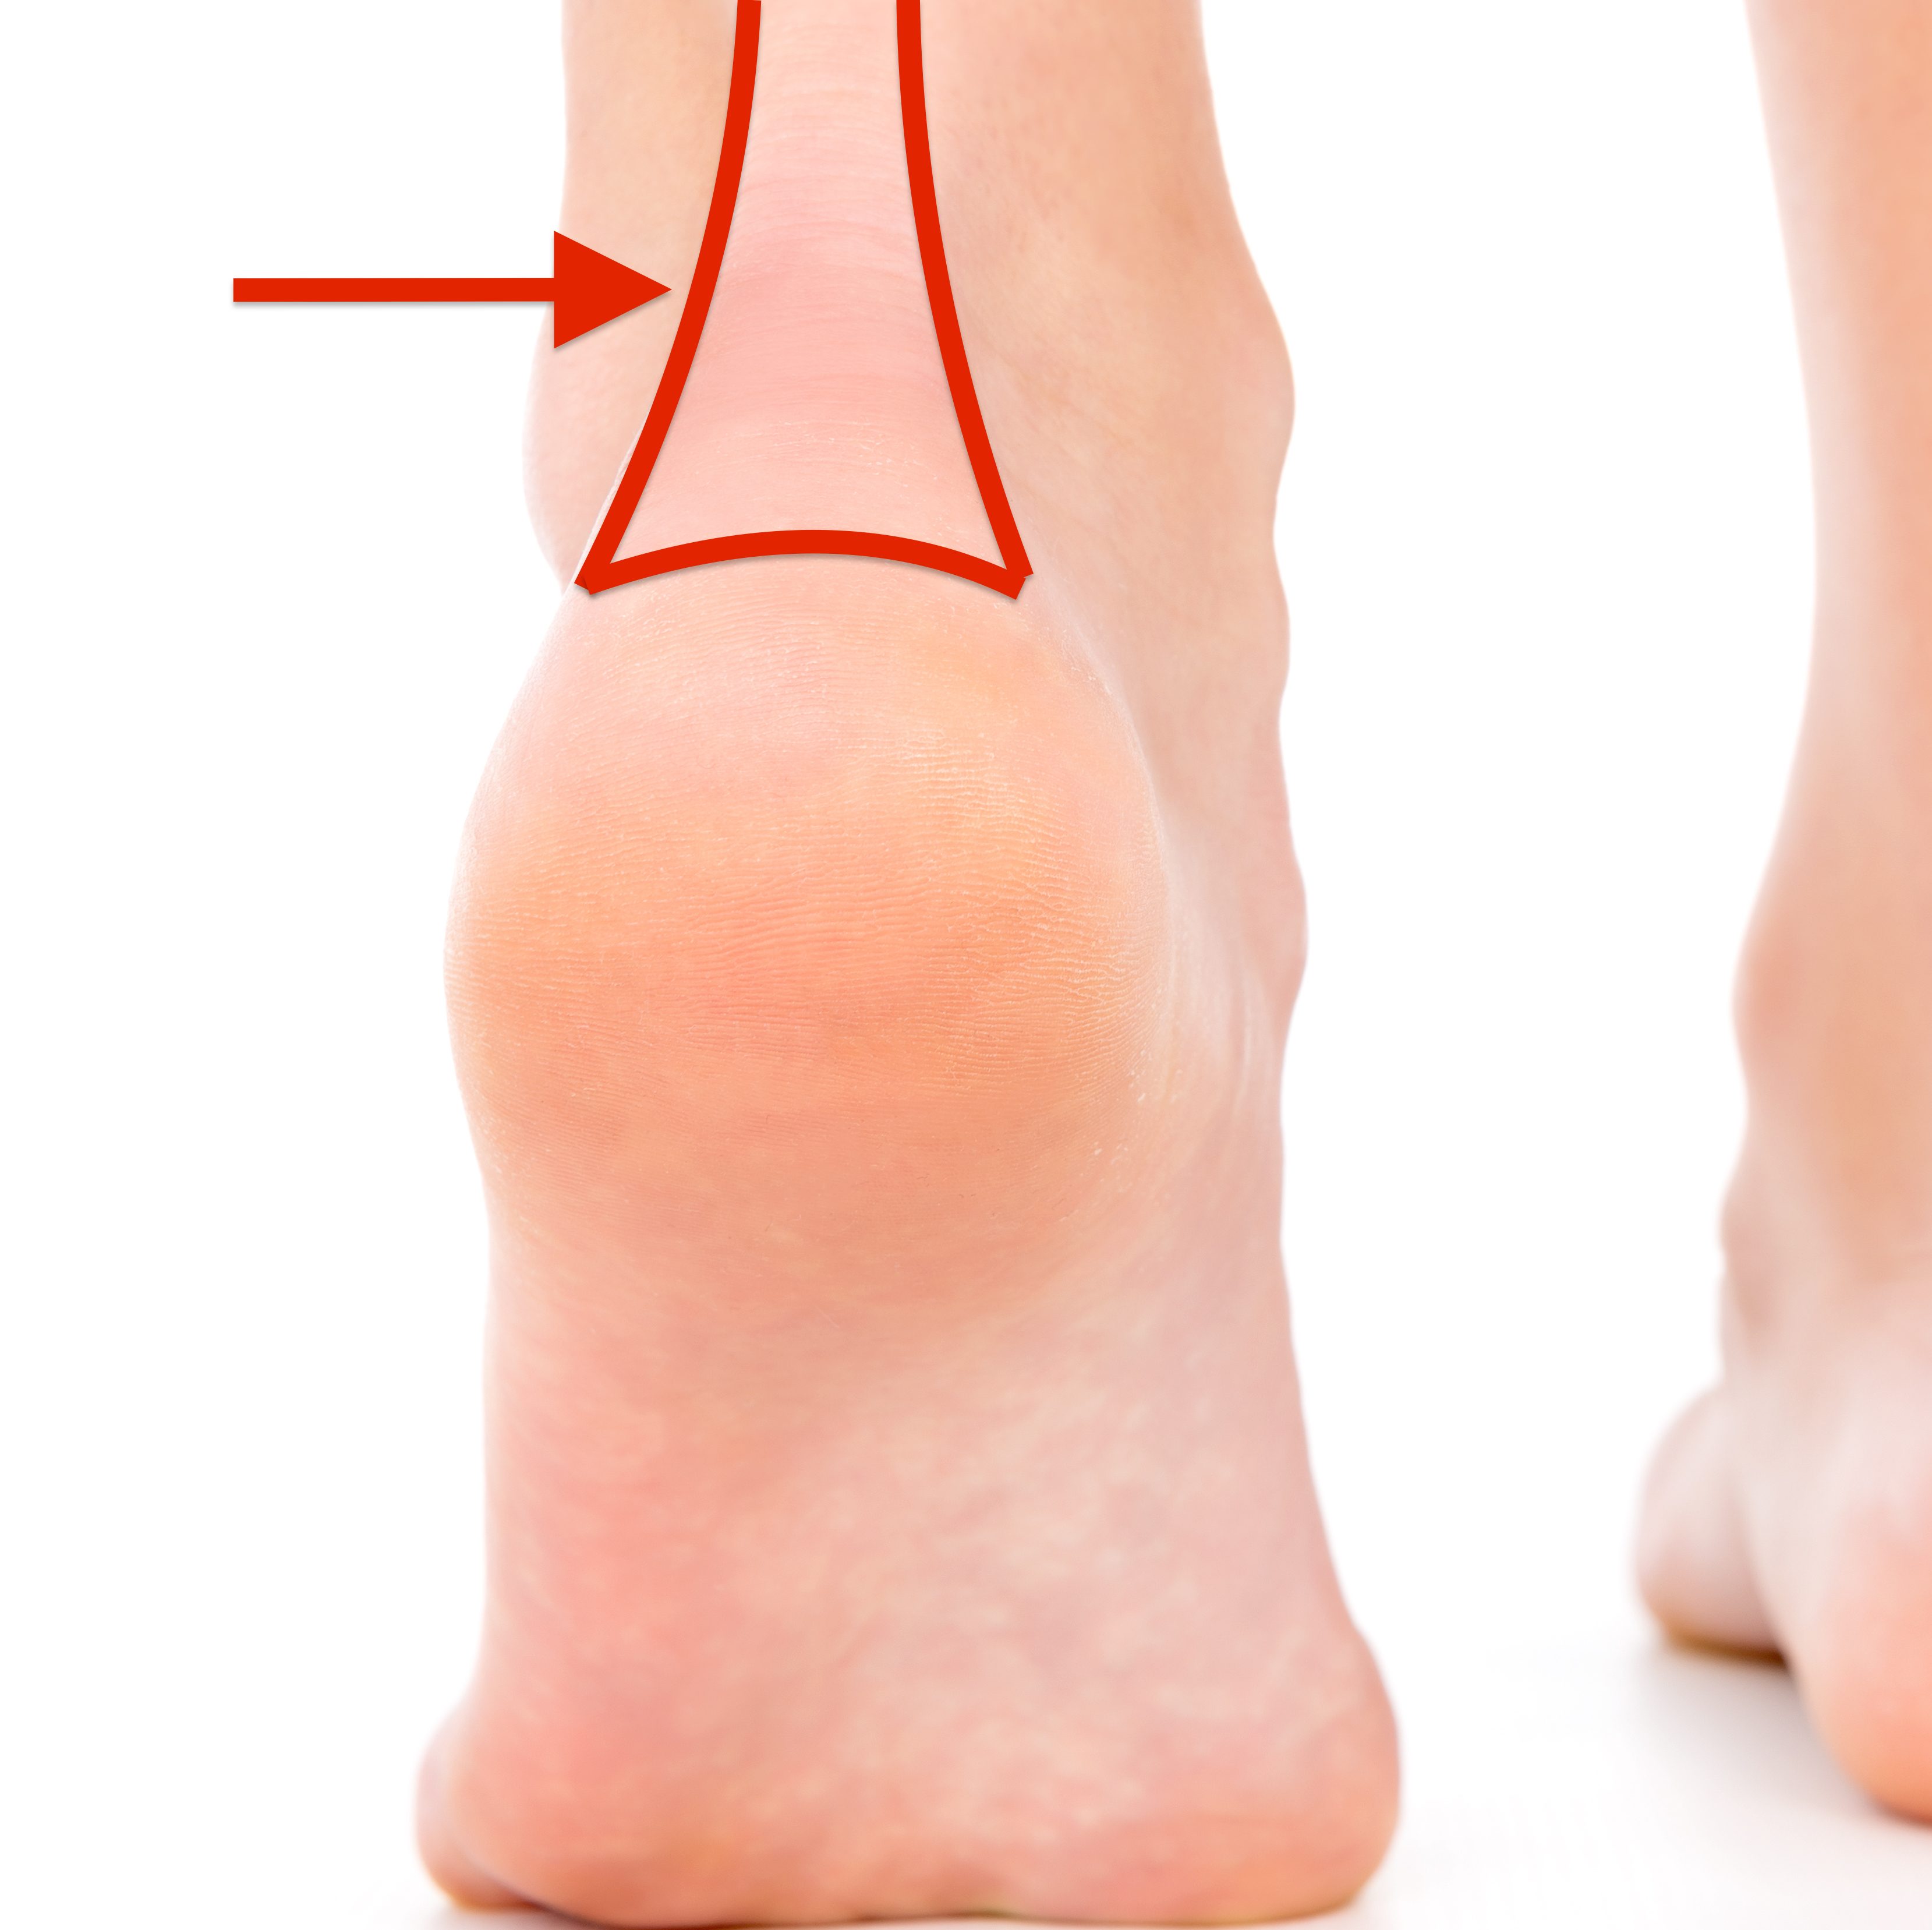

Covering all the common injuries and pain our feet and ankles experience over a lifetime. Click on the links below for more information.